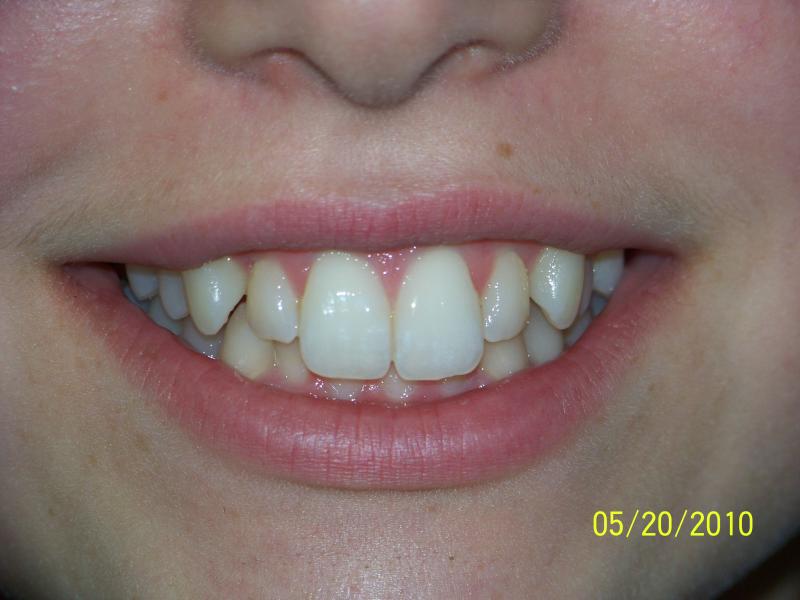

Isabelle G.

Invisalign Case

INVISALIGN, 10 months, 1 series of aligners to correct alignment, deep overbite and shift teeth to the right to match upper and lower mid line, TOTAL TREATMENT TIME: 10 months COSMETIC DENTISTRY: incisal reduction of anterior teeth before and after Invisalign.

Deep Overbite, Teeth Reshaping, Testimonial